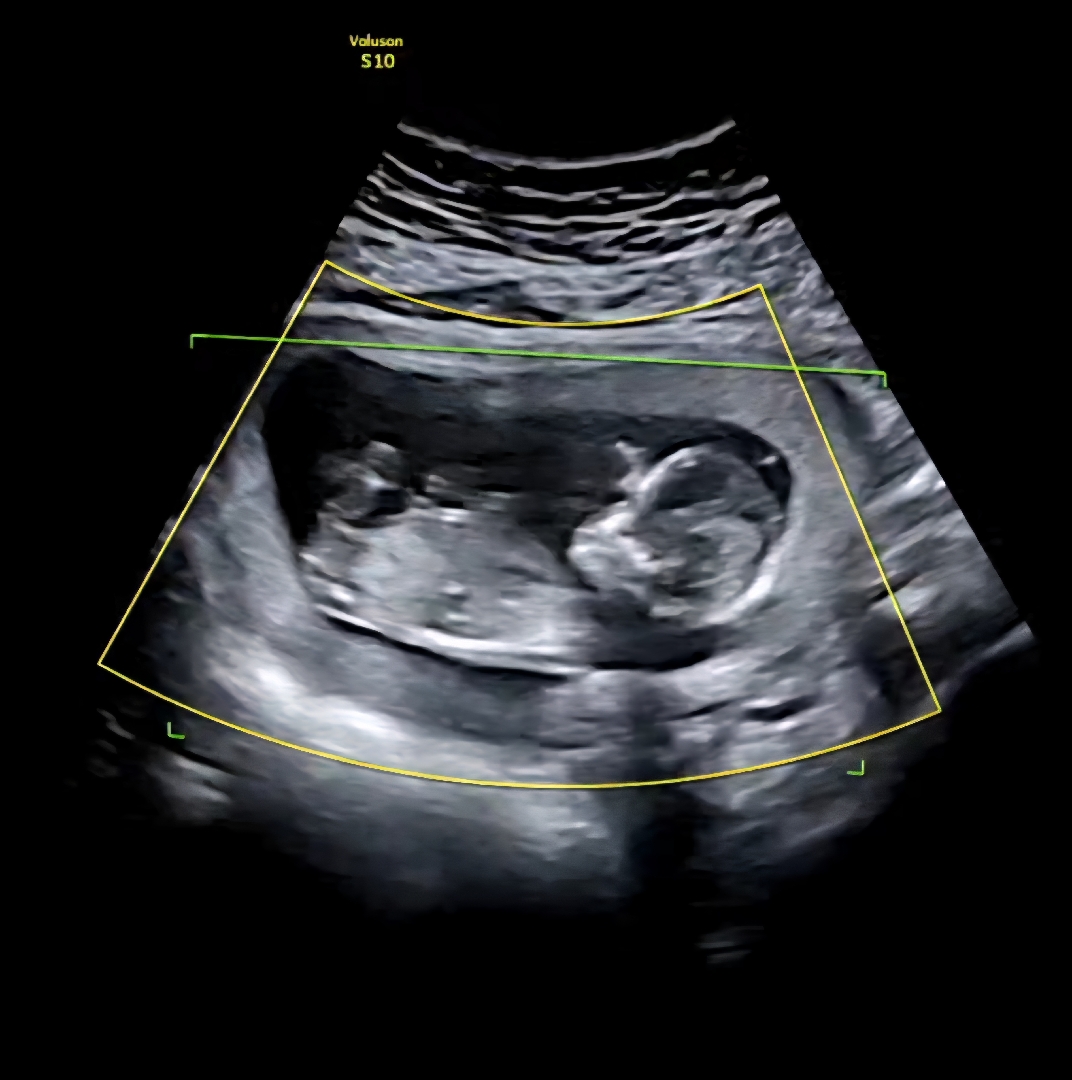

13주 1일 각도법 봐주세여!!!

아들일까요 딸일까요 궁금해서요 잘 아시는 분 부탁드려요~~!

사진이 너무흐려서 긴가민가한데 딸같아보여용 저두 각도법보던게 엊그제갔던데 벌써애기8갤이네여ㅋㅋ 그때가그립네여

아들 한표요!